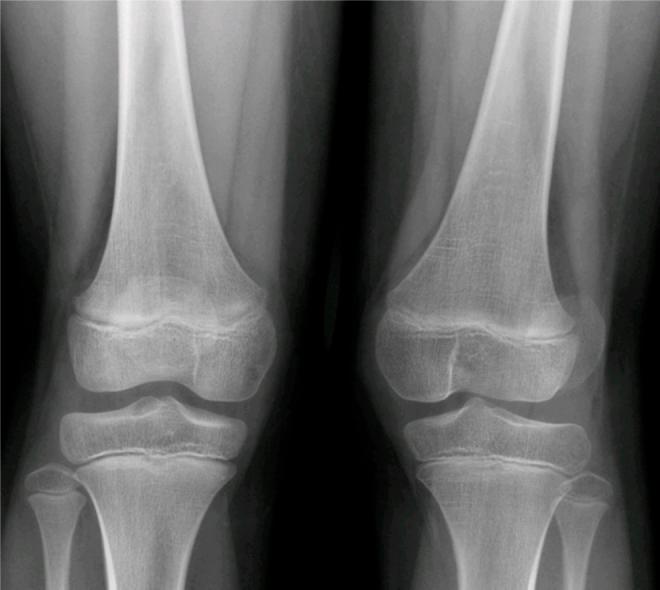

Congenital patellar dislocation is a rare condition in which the patella is permanently dislocated and cannot be reduced manually. The patella develops normally as a sesamoid bone of the femur. This congenital dislocation results from failure of the internal rotation of the myotome that forms the femur, quadriceps muscle and extensor apparatus. It usually manifests immediately after birth, although in some rare cases, the diagnosis may be delayed until adolescence or adulthood. Early diagnosis is important, thereby allowing surgical correction and avoiding late sequelae, including early degenerative changes in the knee. A case of permanent dislocation of the patella is presented here, in a female child aged seven years.

先天性髌骨脱位是一种罕见的病症,即髌骨永久性脱位且无法手法复位。髌骨作为股骨的籽骨正常发育。这种先天性脱位是由于形成股骨、股四头肌和伸肌装置的肌节内旋失败所致。它通常在出生后立即出现,不过在一些罕见病例中,诊断可能会延迟至青春期或成年期。早期诊断很重要,这样才能进行手术矫正并避免晚期后遗症,包括膝关节的早期退行性改变。本文介绍了一例七岁女童永久性髌骨脱位的病例。